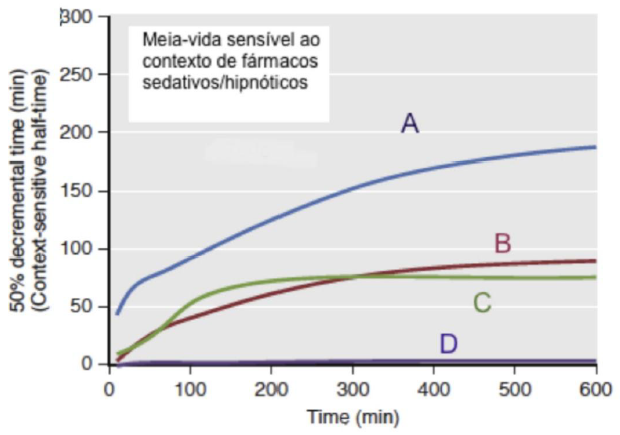

Considere as informações contidas no seguinte gráfico para responder à questão. O gráfico descreve a meia-vida sensível ao contexto de quatro hipnóticos/ sedativos: Tiopental, Dexmedetomidina, Midazolam e Propofol (não necessariamente nessa ordem).

Assinale a alternativa CORRETA: